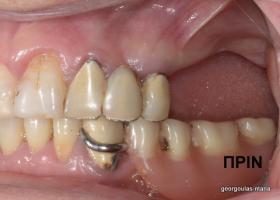

ΟΛΙΚΗ ΑΠΟΚΑΤΑΣΤΑΣΗ ΑΝΩ Κ ΚΑΤΩ ΓΝΑΘΟΥ ΜΕ ΕΜΦΥΤΕΥΜΑΤΑ, ΑΜΕΣΗ ΦΟΡΤΙΣΗ Κ ΑΝΟΙΚΤΗ ΑΝΥΨΩΣΗ ΙΓΜΟΡΕΙΟΥ

Η ασθενής αυτή είχε παλιές ακίνητες αποκαταστάσεις (γέφυρες) στην άνω γνάθο  κ μια κινητή προσθετική αποκατάσταση (μερική οδοντοστοιχία-"μασελάκι") στην κάτω γνάθο. Ήταν δυσαρεστημένη τόσο με την εμφάνιση όσο και με τη λειτουργία των δοντιών της καθώς παραπονιόταν ότι  είχαν εντονη κινητικότητα ενώ και οι προσθετικές τους εργασιές δεν ήταν σταθερές. Η πρόγνωση των δοντιών κρίθηκε φτωχή με αποτέλεσμα να μην είναι δυνατή η συμμετοχή τους σε μια νεα προσθετική αποκατάσταση με μακροχρόνια διάρκεια. Η ασθενής επιθυμούσε οι νέες αποκαταστάσεις να είναι σταθερές και ακίνητες.  Για το λόγο αυτό αποφασίστηκε η ολική αποκατάσταση της άνω κ κάτω γνάθου με ακίνητες επιεμφυτευματικές εργασίες. Στην αριστερή πλευρά της άνω γνάθου, λόγω μη επαρκούς οστού για την τοποθέτηση εμφυτευμάτων προηγήθηκε επέμβαση ανοιχτής  ανύψωσης ιγμορείου άντρου με τη χρήση πιεζοχειρουργικού μηχανήματος ώστε να δημιουργηθεί το κατάλληλο οστικό υπόστρωμα. Ακολούθησε σε επόμενο χειρουργείο η εξαγωγή των υπάρχοντων δοντιών κ η άμεση τοποθέτηση εμφυτεύματων (άμεση εμφύτευση) κ δύο μέρες μετά η τοποθέτηση προσωρινής εργασίας επί των εμφυτευμάτων (άμεση φόρτιση) με αποτέλεσμα η ασθενής να μη μείνει καθόλου χωρίς δόντια κ να είναι καλυμένη αισθητικά όσο καιρό διήρκησε η εργασία